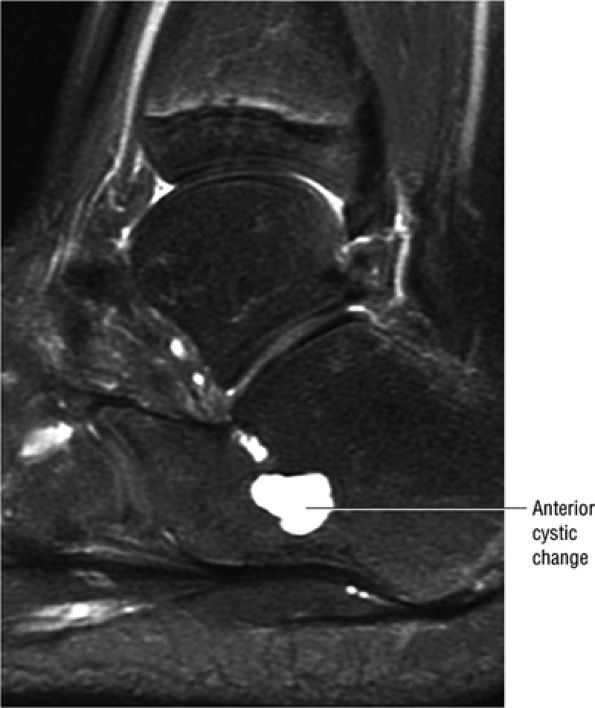

FIGURE 5.91 ● Anterior calcaneus cystic change. Prominent vascular remnants near the attachment of the cervical and interosseous ligaments are associated with hyperintensity on FS PD FSE images through the lateral aspect of the calcaneus.